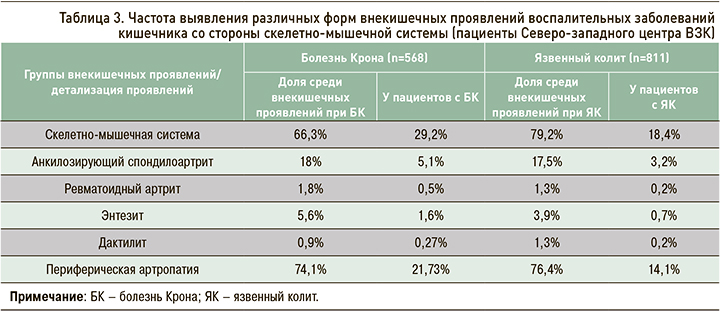

Среди пациентов Северо-западного центра ВЗК скелетно-мышечные симптомы как внекишечные проявления ВЗК отмечаются у 29,2% больных с Болезнью Крона и 18,4% с язвенным колитом и являются лидирующими в структуре всех внекишечных проявлений (табл. 3). Наиболее частый суставной симптом – периферическая полиартропатия (рис. 8). Второе по численности место среди суставных проявлений занимает более серьезная патология – анкилозирующий спондилоартрит, не связанный с активностью ВЗК и способный приводить к дополнительной инвалидизации.

Вовлечение суставов при ВЗК, по данным литературы, является наиболее частым внекишечным проявлением с распространенностью 6–46% (20–50% для осевой артропатии и 5–20% для периферического артрита соответственно). В некоторых источниках сообщается, что распространенность суставных внекишечных проявлений ВЗК может уменьшаться с возрастом. В результатах метаанализа, проведенного Karreman M.C. et al., указывается частота суставных проявлений ВЗК 25% для возрастной группы 20–30 лет и 2% для пациентов возраста 50–60 лет [33].

Структура симптоматики со стороны опорно-двигательного аппарата неоднородна: в патологический процесс могут вовлекаться как осевые, так и периферические суставы. ВЗК-ассоциированный энтезит, заключающийся в воспалении места прикрепления сухожилия к кости и приводящий к эрозированию и пролиферации костной ткани, клинически проявляется болевым синдромом и отеком. Частота выявления энтезитов при ВЗК указывается различными авторами в широком диапазоне – от 6 до 54%. Дактилиты, которые представляют собой сосископодобное опухание пальцев рук или ног, характерное для спондилоартрита вне ВЗК, встречается у 2–5% больных ВЗК [34]. Взаимосвязь клинической интенсивности энтезитов и дактилитов с активностью воспалительного процесса в кишке на сегодняшний день изучена недостаточно [35].

Среди аксиальных воспалительных артропатий принято различать анкилозирующий спондилоартрит, характеризующийся воспалительной болью в спине и наличием МРТ-признаков сакроилеита/спондилита (частота выявления при ВЗК – 1–12%), и изолированный сакроилеит (частота выявления при ВЗК – 16–46%) [33, 36, 37].